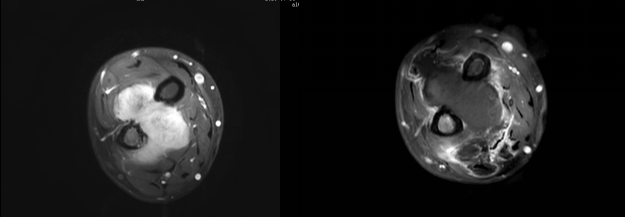

患者3年前無明顯誘因下出現右前臂腫脹,伴壓痛,程度不劇,至當地醫(yī)院就診,查MR提示:右前臂軟組織腫塊。遂行手術。術后病理示:右腕部梭形細胞腫瘤或瘤樣病變,結合免疫組化及影像學結果,考慮侵襲性纖維瘤病。2年前患者無明顯誘因下出現右前臂腫脹,隱痛,夜間加劇,伴皮溫升高,遂至我院就診,超聲提示右前臂尺橈骨間腫塊,考慮復發(fā)可能。患者行腋窩局部神經阻滯下HIFU治療,術后復查腫塊消融約90%。

侵襲性纖維瘤 治療前MRI增強,治療后1天MRI增強